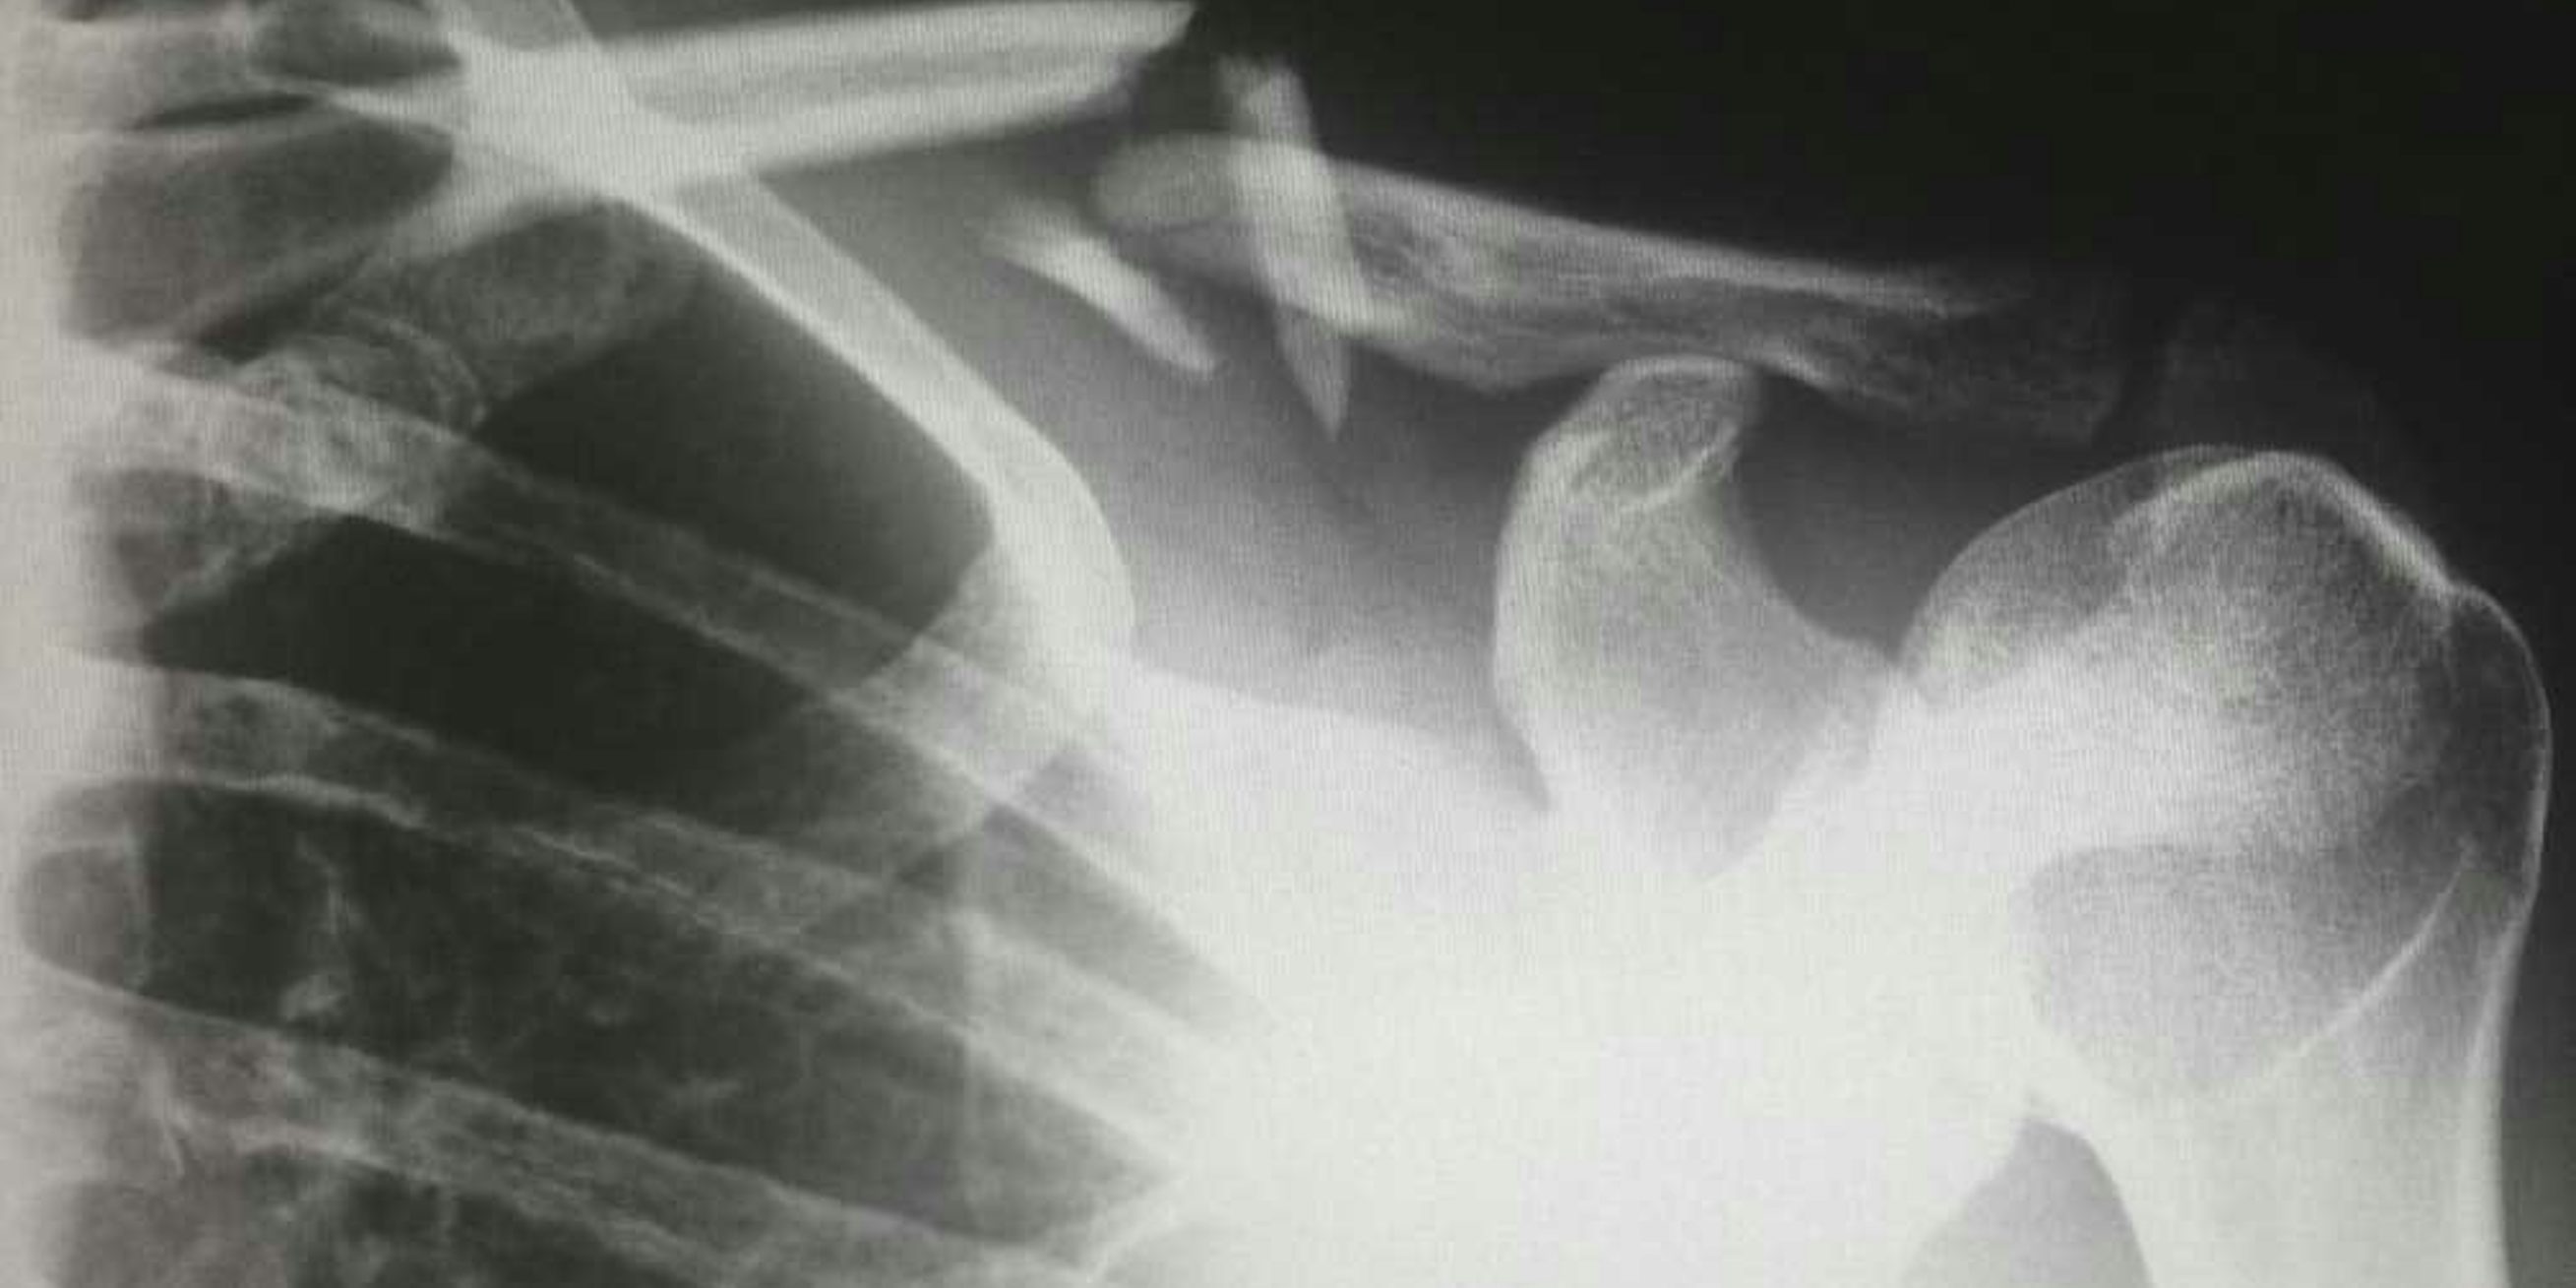

Dijbeenbreuken

Een dijbeenbreuk is een breuk in het dijbeen. Dit kan gebeuren door een trauma, zoals een val of een auto-ongeluk. Dijbeenbreuken zijn vaak ernstig en vereisen een operatie om het bot te herstellen. Herstel kan lang duren, afhankelijk van de ernst van de breuk en de algemene gezondheid van de persoon.

Data van het Nederlands Letsel Informatie Systeem (LIS) laten zien dat dijbeenbreuken vaker voorkomen bij ouderen, vooral als gevolg van vallen. Osteoporose, een aandoening die de botten verzwakt, speelt hierbij een belangrijke rol.